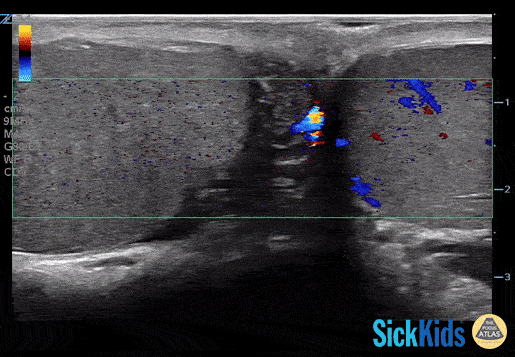

Decreased color doppler is seen in this pediatric patient with testicular torsion. Dr. Lianne McLean (@doctorlianne) FRCPC of the PEM POCUS Group: Division of Emergency Medicine in the Hospital for Sick Children (@epocus)